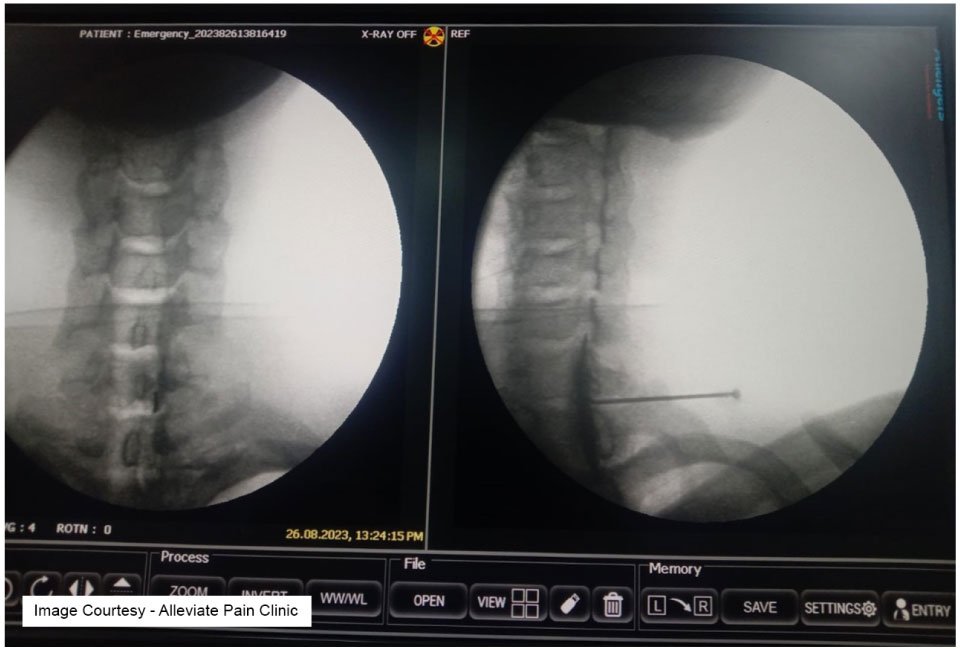

Cervical Epidural Injections

Cost at Alleviate Pain Clinic: Rs 30,000-45,000 (varying based on the number of injections and additional services)Cervical epidural injections target pain in the neck and upper back area. They are highly effective in providing relief from conditions like herniated discs and spinal stenosis. The affordability of these injections at Alleviate Pain Clinic makes them an attractive option for individuals seeking non-surgical solutions to their back pain.